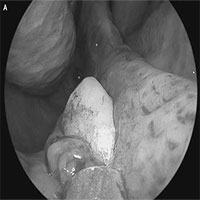

Khó thở nhiều năm, người đàn ông đi khám thì phát hiện vật kỳ lạ này mọc ngay trong mũi

Tình trạng khó thở nhiều năm hóa ra lại có một lời giải thích kỳ lạ hơn bất kỳ thứ gì mà bạn có thể tưởng tượng được.